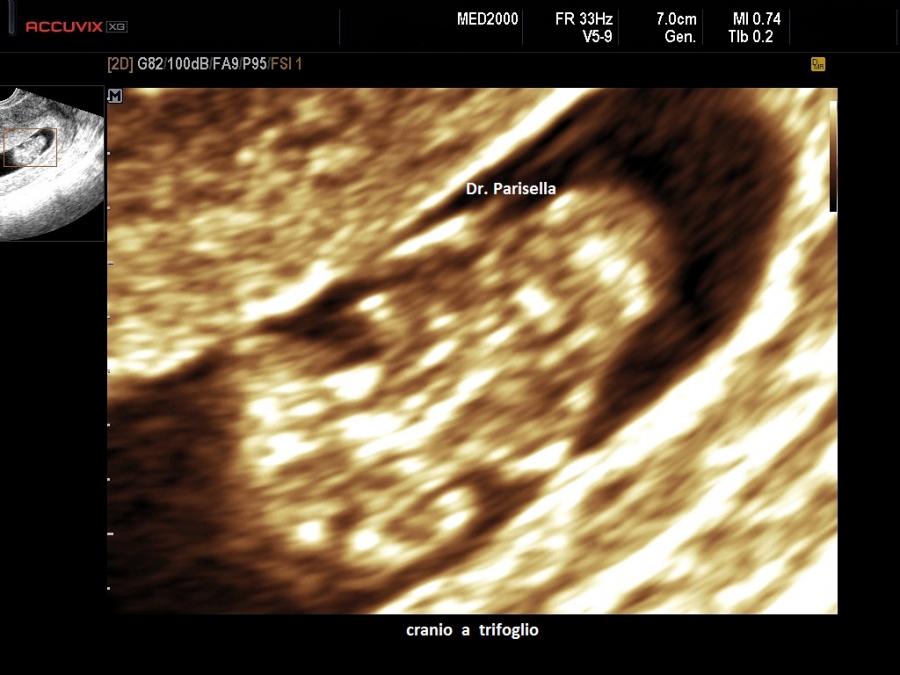

Sindrome del cranio a trifoglio - Kleeblattschaedel Syndrome

La sindrome del cranio 'a trifoglio' è una rara malformazione causata dalla chiusura prematura di tutte le suture craniche. Sono stati osservati finora solo 120 casi, con una prevalenza maggiore nel sesso femminile.

Il segno ecografico principale, cioè il cranio a trifoglio, si associa a dismorfismi facciali (orecchie ad impianto basso, esoftalmo, ipertelorismo, radice nasale appiattita e ipoplasia della parte mediana del viso),  idrocefalo e altre malformazioni cerebrali e cerebellari.